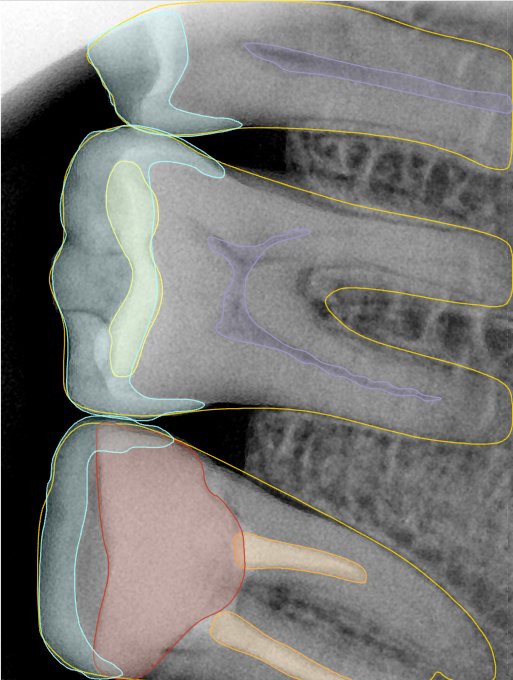

第二版算法问题测试

| 第一版 | 第二版 | 是否解决 | |

|---|---|---|---|

![]() | ![]() ![]() 边角识别有问题 龋齿识别不全 牙髓识别不全 | ![]() | 解决 |

![]() | ![]() 边角识别有问题 识别信息有误 自查(牙冠识别不全) | ![]() | 解决 |

![]() | ![]() ![]() 边角识别有误 大范围填充识别遗漏 | ![]() | 解决 |

![]() | ![]() 识别信息不全 | ![]() | 解决 |

![]() | ![]() ![]() 边角问题 牙胶识别不全 牙冠识别不全 | ![]() | 解决 |

![]() 换图片 | ![]() | ![]() 牙冠部分稍微白了一些就识别成小范围修补,部分判断异常 | 部分解决,修复类略敏感,牙冠部分稍微白了一些就识别成小范围修补,部分判断异常。 |

![]() | ![]() ![]() 牙冠识别不全 牙髓不全 根尖炎龋齿识别有误 | ![]() | 解决 |

![]() | ![]() | ![]() | 解决 |

![]() 换图片 | ![]() | ![]() | 解决 |

![]() | ![]() 牙冠识别有误 | ![]() | 解决 |

![]() 换图片 | ![]() ![]() 边角识别有误 | ![]() 修复类敏感 | 部分解决,图像过白,导致修复类判断异常。 |

![]() 换图片 | ![]() 牙冠识别不全 | ![]() 修复类敏感 | 部分解决,图像过白,导致修复类判断异常 |

结论:修复类出现了不鲁棒的情况,后续需要加入轮廓的扩充数据进行增强。